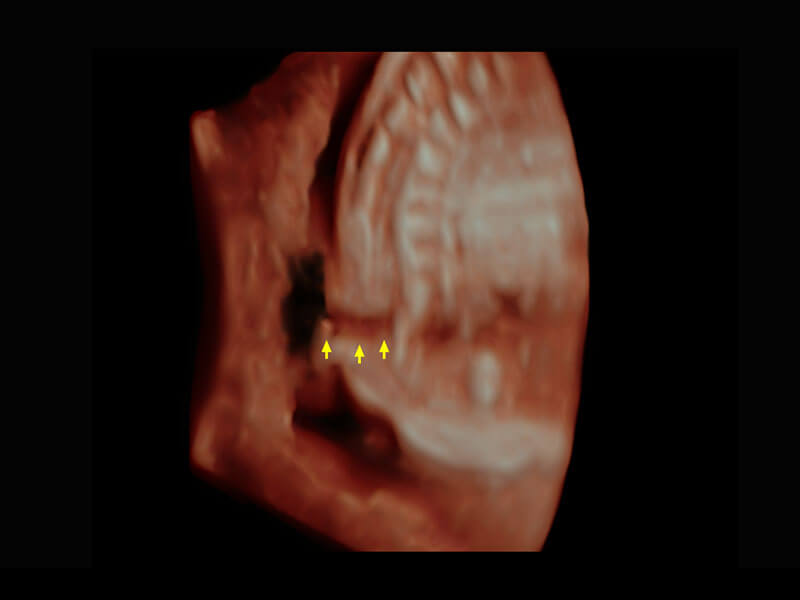

胎心筛查

P60搭载一系列胎儿心脏成像技术,实现精细的胎儿心脏评估。

• 四腔切面

• 四腔心血流

• 右室双出口

• 胎心容积成像